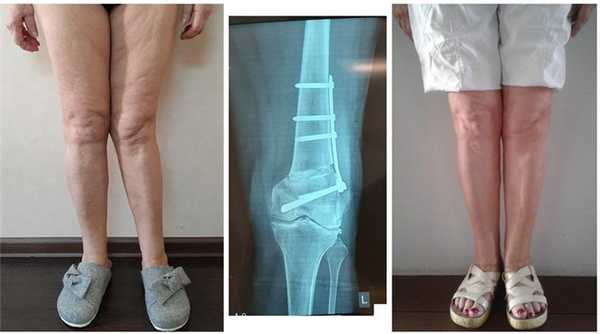

Внешний вид пациентки 19 лет до и после комбинированной коррекции

(угловая коррекция + медиализация + ротация + удлинение голеней на 3 см).

Справа - рентгенограммы в процессе коррекции